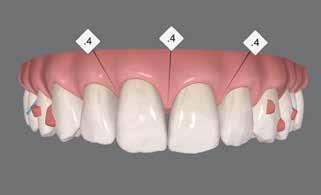

Der planlægges alignerbehandling af begge kæber med intrusion af 1+1 og 2,1-1,2, nivellering af trangstilling UK med interproksimal reduktion (IPR) (Fig. 2 A, B) og senere IPR OK for reduktion af dark triangles mellem incisiverne efter nivellering. Patienten instrueres i at benytte alignere 20-22 timer/ dag med alignerskift hver 7. dag, og patienten ses hver 3.-8. uge under forløbet. Den første alignerserie består af 16 alignere for nivellering OK/UK og IPR i UK (Fig. 2). Efter denne serie planlægges IPR mellem incisiverne i OK for reduktion af dark triangles (Fig. 3) samt yderligere intrusion af OK og UK-fronten i 12 refinement-alignere. Patienten udviser god kooperation og er meget tilfreds med alignerapparaturet, som er mindre synligt end det faste apparatur (Fig. 4).